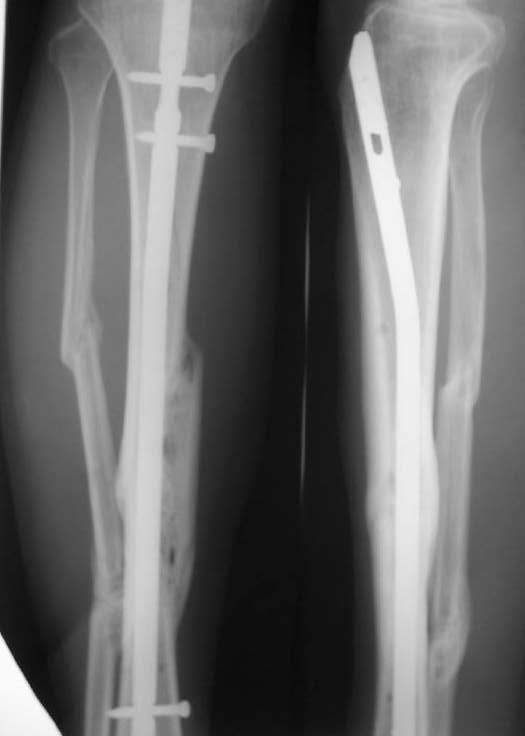

При невозможности или чрезмерной травматичности одномоментного восстановления длины можно пойти двухэтапно (аппарат, потом гвоздь). Похожий пример см. тут. Прошло уже года полтора после остеосинтеза. Может, коллега Зырянов покажет годичный результат, если есть?

Отправитель: Сергей Зырянов 16 Декабрь 2005, 08:20

Александр Николаевич, к сожалению больной не является на контрольные осмотры. Я последний раз видел больного, когда прошло 7 месяцев после операции БОС. У него все хорошо. Каких либо жалоб и ограничений в нагрузке нет. Высылаю снимки до операции и последние снимки.